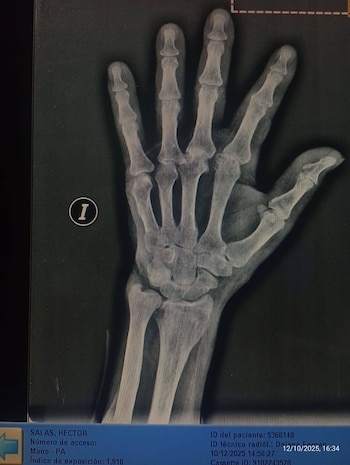

En su publicación de Facebook, no solo adjuntó imágenes de su abuelo golpeado, sino también el video de las cámaras privadas del establecimiento, donde puede verse la secuencia de la agresión, además de las radiografías que debió realizarse tras el ataque.

De acuerdo con la familia del anciano, en un control médico que solicitaron las nietas se constataron fracturas en la mano derecha -en particular, en el dedo pulgar- y heridas en el rostro del hombre. “Están en un estado de vulnerabilidad terrible, sin nadie que los proteja”, lamentaron, al respecto del episodio.